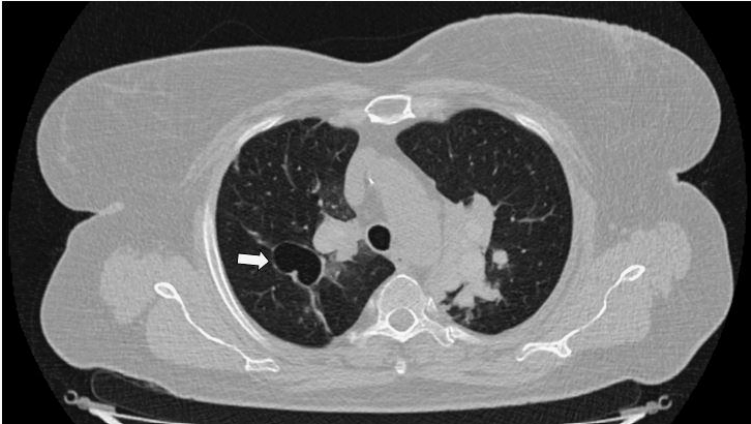

胸部CT:中央支气管扩张(圆柱状支气管扩张)(图2),扩张支气管内可见均匀高密度区,可能为高密度黏液影(hyperattenuating mucus,HAM)(图3、4),周围可见吸收性/阻塞性肺不张,累及双上叶和右中叶。肺门周围区域中央段支气管近端变窄(可能因黏液堵塞而继发),双肺上叶可见少量大小不一的小叶中心结节。结合以上,其影像学表现与变应性支气管肺曲霉病(Allergic Bronchopulmonary Aspergillosis,ABPA)相符。

图2 非增强CT示中央支气管扩张(白色箭头)